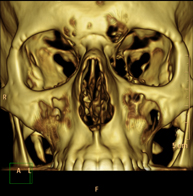

Prova radiològica que consisteix en obtenir imatges de la hipòfisi cerebral d'alta definició anatòmica, mitjançant l'ús d'un equip de TC (Tomografia Computeritzada). Indicacions: sospita de tumor hipofisari, trastorn del creixement. - TC Massís facial

Prova radiològica que consisteix en obtenir imatges del massís facial (cara) d'alta definició anatòmica, mitjançant l'ús d'un equip de TC (Tomografia Computeritzada). Indicacions: tumors, cirurgia plàstica. - TC Oïda